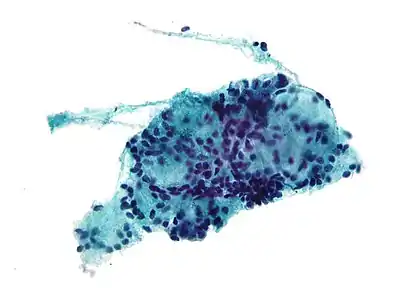

Micrograph of adenoid cystic carcinoma, fine needle aspiration specimen, Pap stain